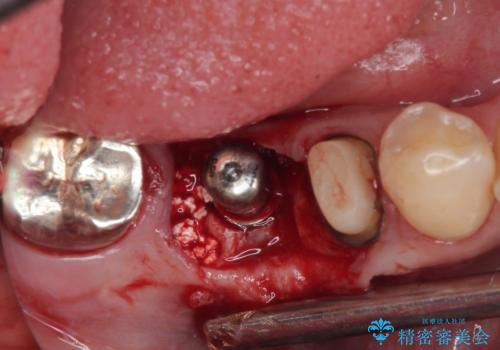

左下小臼歯は根管治療で対応する予定でしたが、診断のために歯肉を開いたところ頬側に垂直破折が認められたため、抜歯即時埋入インプラントによる補綴治療を選択することとしました。

インプラント埋入時に十分な安定値を得ることができたため、速やかに仮歯を装着し、最小限の通院回数で治療を終えることができました。